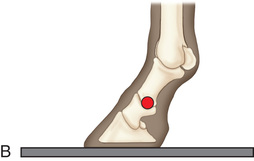

The distal phalanx and the navicular bone comprise the digit or foot. Common indications for imaging the equine foot include localized lameness by clinical examination (pain on pressure from foot testers, increased digital pulses, etc.) or by diagnostic analgesia, laminitis, penetrating wounds, or as required for a prepurchase examination.1

Digit/foot: P-III (distal phalanx, coffin bone) P-II (middle phalanx) P-I (proximal phalanx-pastern) Proximal interphalangeal joint (pastern joint) joint | DP (Standard) (Fig. 24.62B,C) | Dorsal 45-degree proximal–palmarodistal (D45Pr-PaDi) | Foot slightly forward on image receptor. | Perpendicular to foot axis at MSP (midsagittal plane) at area of interest with beam angled ~45 degrees to ground |